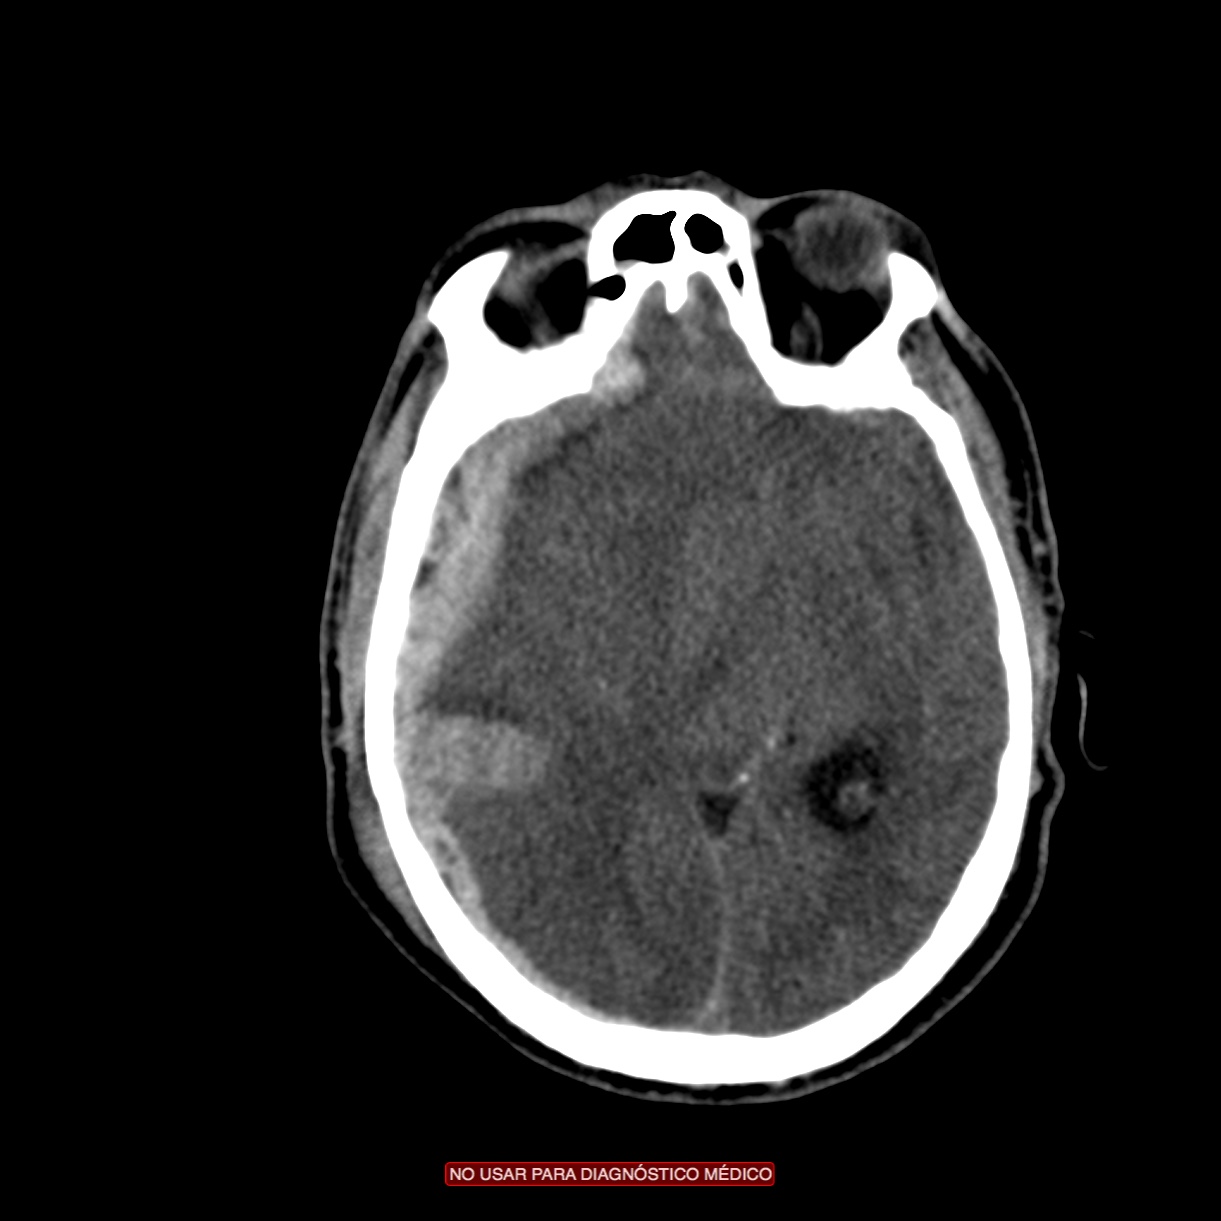

HEMORRAGIAS INTRA AXIALES.

Contusiones.

- Son las lesiones más frecuentes tras un traumatismo, especialmente en personas mayores.

- Son la expresión de laceraciones del parénquima cerebral tras un golpe o contragolpe, dónde suelen ser de mayor tamaño.

- Focos hiperdensos uni o multifocales parcheados y mal definidos. De localización cortical (trauma leve) y/o subcortical (trauma más severo).

- Lóbulo frontal y temporal son localizaciones más frecuentes debido a que el cerebro se desliza sobre la superficie irregular de la fosa craneal anterior y media.

Nota: La contusión y el hematoma constituye el mismo espectro de daños. Las contusiones hemorrágicas se definen como pequeñas hiperdensidades que afecta preferentemente el córtex con o sin edema periférico con relativa normalidad de la sustancia blanca subyacente en el trauma leve. Pueden incrementar en tamaño con el tiempo, lo que se conoce como progresión hemorrágica.